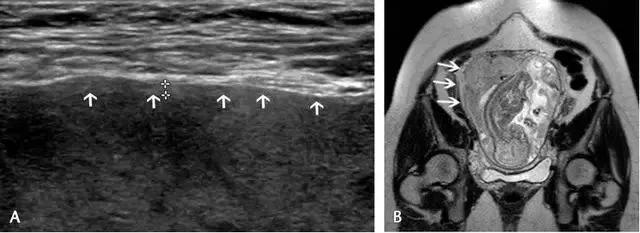

胎盘附着异常:包括胎盘粘连、胎盘植入及胎盘穿透(图 11)。胎盘粘连指胎盘组织向子宫肌壁延伸,但并未对其构成实质性的侵袭,占所有胎盘附着异常的75%。

胎盘植入指胎盘组织已侵入子宫肌壁,但并未突破浆膜层。穿透指不仅侵入肌壁,且已突破至浆膜层之外,可导致子宫的毗邻器官如膀胱、肠管及腹壁受累。超声是本病的主要显像方法,在临床高度怀疑本病或超声检查为阴性或不确定时,可使用 MRI(图 12 和图 13)。

图 12 示胎盘粘连:A 为孕 32 周患完全性前置胎盘(此图未显示)孕妇的子宫前壁横切面(线阵探头所得),可见肌壁由上至下、向膀胱子宫陷凹方向逐渐缺乏、变薄(短箭头所示)。B 为另一孕妇的冠状位 MRI,孕期经常性左腹痛,超声考虑胎盘粘连,长箭头示胎盘下方的低信号肌壁由左向右逐渐变薄。此 2 例均在剖腹产时被证实为胎盘粘连

图 13 示合并有完全性前置胎盘的胎盘穿透,患者有 2 次剖宫产病史:A 为子宫纵切面,箭头示肌壁逐渐变薄、子宫与膀胱之间的界限模糊,胎盘下的闲置空间消失(B :膀胱)。B 为同一患者的子宫矢状面,箭头示大量不规则紊乱血流向肌壁延伸。图 C 为另一孕妇 28 周时的矢状位 MRI,可见前次剖腹产瘢痕上缘存在胎盘对子宫前壁的侵犯、肌壁连续性局部中断(箭头)